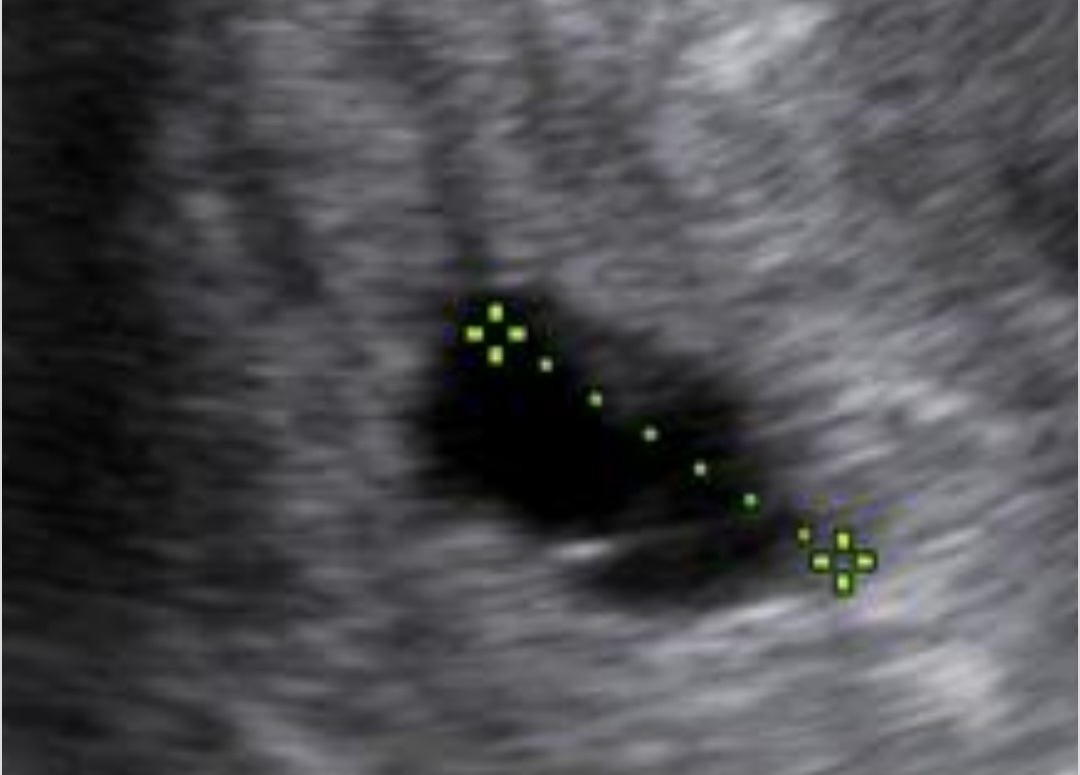

سلام دکتر این دو سونوی من بافاصله دوهفتس. امکان داره جنین خودش جذب بشه؟

دکتر لطفا عکس خود ساک رو نگاه کنید ممنون

این عکس سونو نگاه کنید دکتر خالیه واقعا جنین کامل جذب شده؟